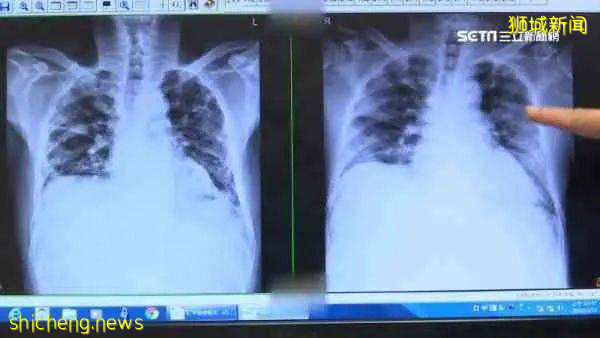

大部分人患上新冠后大抵是无症状或者是轻症,不会对人体造成类似肺纤维化的这种不可逆损害。

肺纤维化会造成人类肺氧和功能变差,未来更容易感染肺炎,图源:见水印